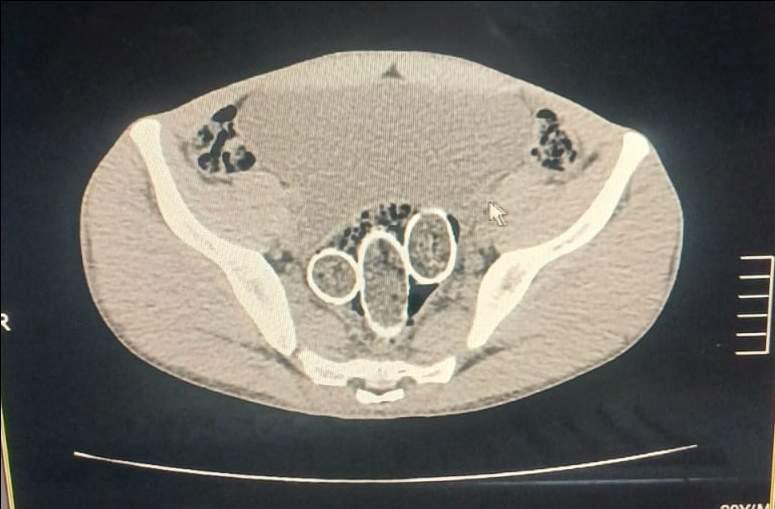

25 Kasım 2024 günü Narkotik Suçlarla Mücadele Şube Müdürlüğümüzce uyuşturucu veya

uyarıcı madde ticareti yapan şahıs veya organizasyonlara yönelik yapılan operasyonda (5) şüpheli

şahıs yakalanmış, iki şahsın yaptırılan iç beden muayenesinde ve kullandıkları iki araçta yapılan

aramada;